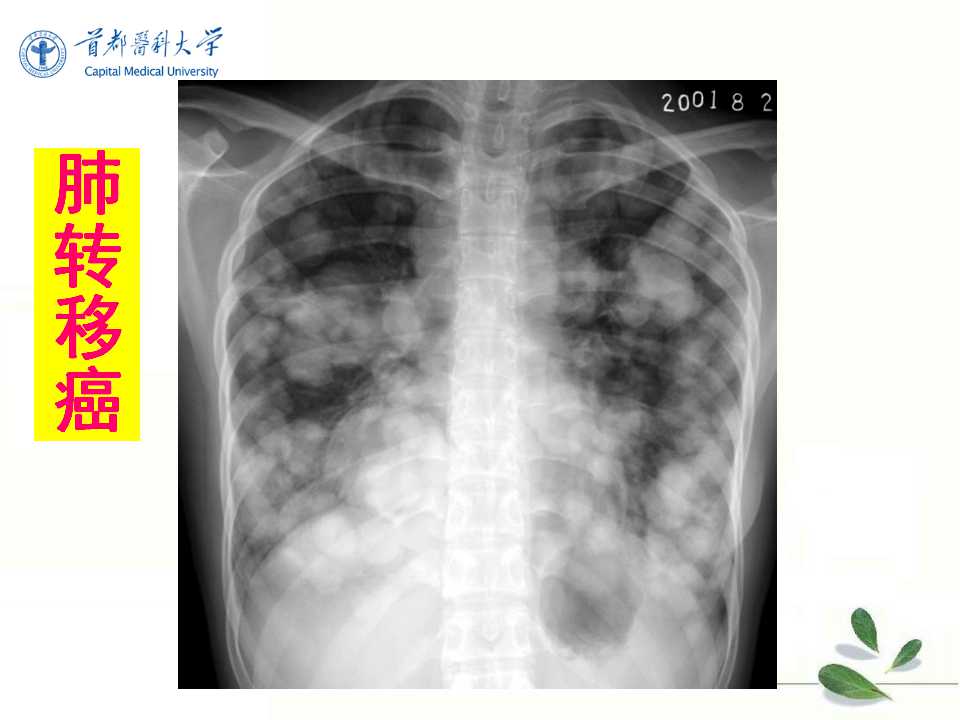

肺癌的影像学检查